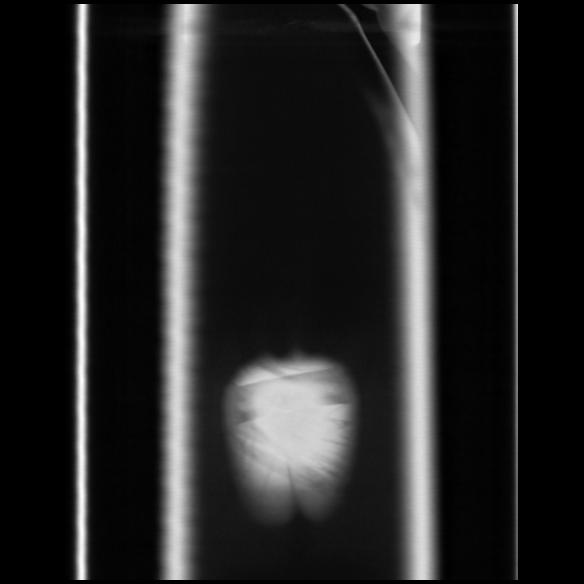

6 CUERPO,CE,Coronal,3.000,CUERPO,Coronal,